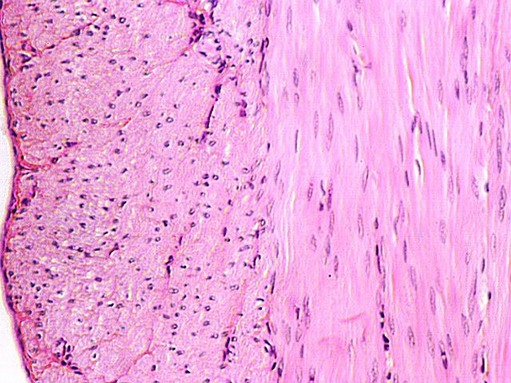

The wall of a muscular artery contains a prominent layer of smooth muscle, running circularly. It is the layer that is most homogeneous just under the "tunica intima". It is called the tunica media. The following two photos are from your skin slide (Slide 25).